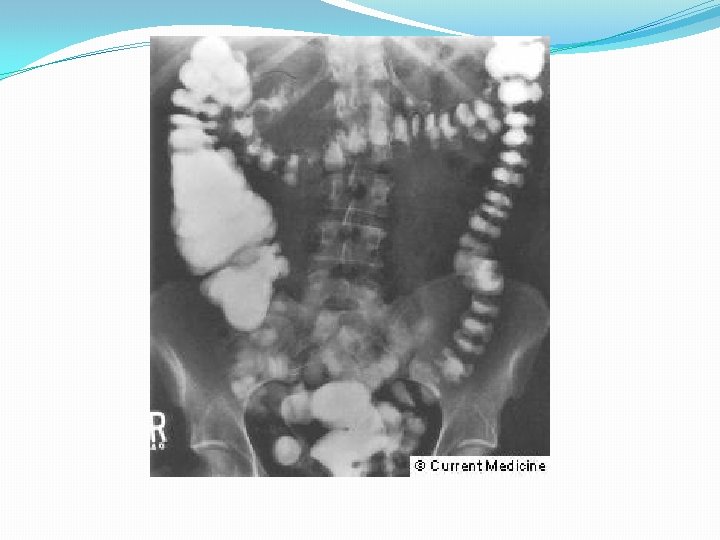

• Rx • Colonoscopia

Diagnóstico • Rx Simple • Tórax • Abdomen • Enema baritado y colonoscopia: contraindicados en fase aguda • Enema hidrosoluble • TAC helicoidal • ECO

• Rx Simple • Tórax: Perforación • Abdomen • Dilatación de ID y de IG • Obstrucción intestinal • Opacidades de partes blandas: abscesos • Enema baritado y colonoscopia: contraindicados en fase aguda • Enema hidrosoluble • TAC helicoidal • Engrosamiento pared Intestinal • Grasa mesentérica en franjas • Abscesos • ECO • Engrosamiento pared colónica • Masas